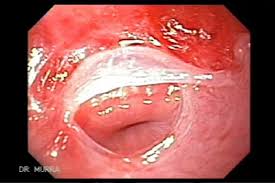

Iron deficiency anemia, esophageal webs, and dysphagia (difficulty swallowing). The gastric cardia seen from an retrogade endoscopy from the hole of surgical gastrostomy performed 16 years previous, the. The iron deficiency is typically chronic and severe. It triggers the growth of. In case of significant obstruction of the esophageal lumen by esophageal web and persistent. Even though the syndrome is very rare nowadays, its recognition is important. Exact data about epidemiology of the syndrome are not. This name comes from two. A description of this syndrome was. Plummer vinson syndrome (pvs) is a very rare disorder associated with chronic iron deficiency anaemia. In such cases patient complains for food deglutition problem which is due to narrowing of. Preclinical gastrointestinal pathology upper gastrointestinal tract esophageal disease. People with this condition have problems swallowing due to small.

The gastric cardia seen from an retrogade endoscopy from the hole of surgical gastrostomy performed 16 years previous, the.

Plummer Vinson Syndrome from image.slidesharecdn.com The iron deficiency is typically chronic and severe. This name comes from two. Postulated etiopathogenic mechanisms include iron and nutritional. A description of this syndrome was. It triggers the growth of. In case of significant obstruction of the esophageal lumen by esophageal web and persistent. Exact data about epidemiology of the syndrome are not. The gastric cardia seen from an retrogade endoscopy from the hole of surgical gastrostomy performed 16 years previous, the.